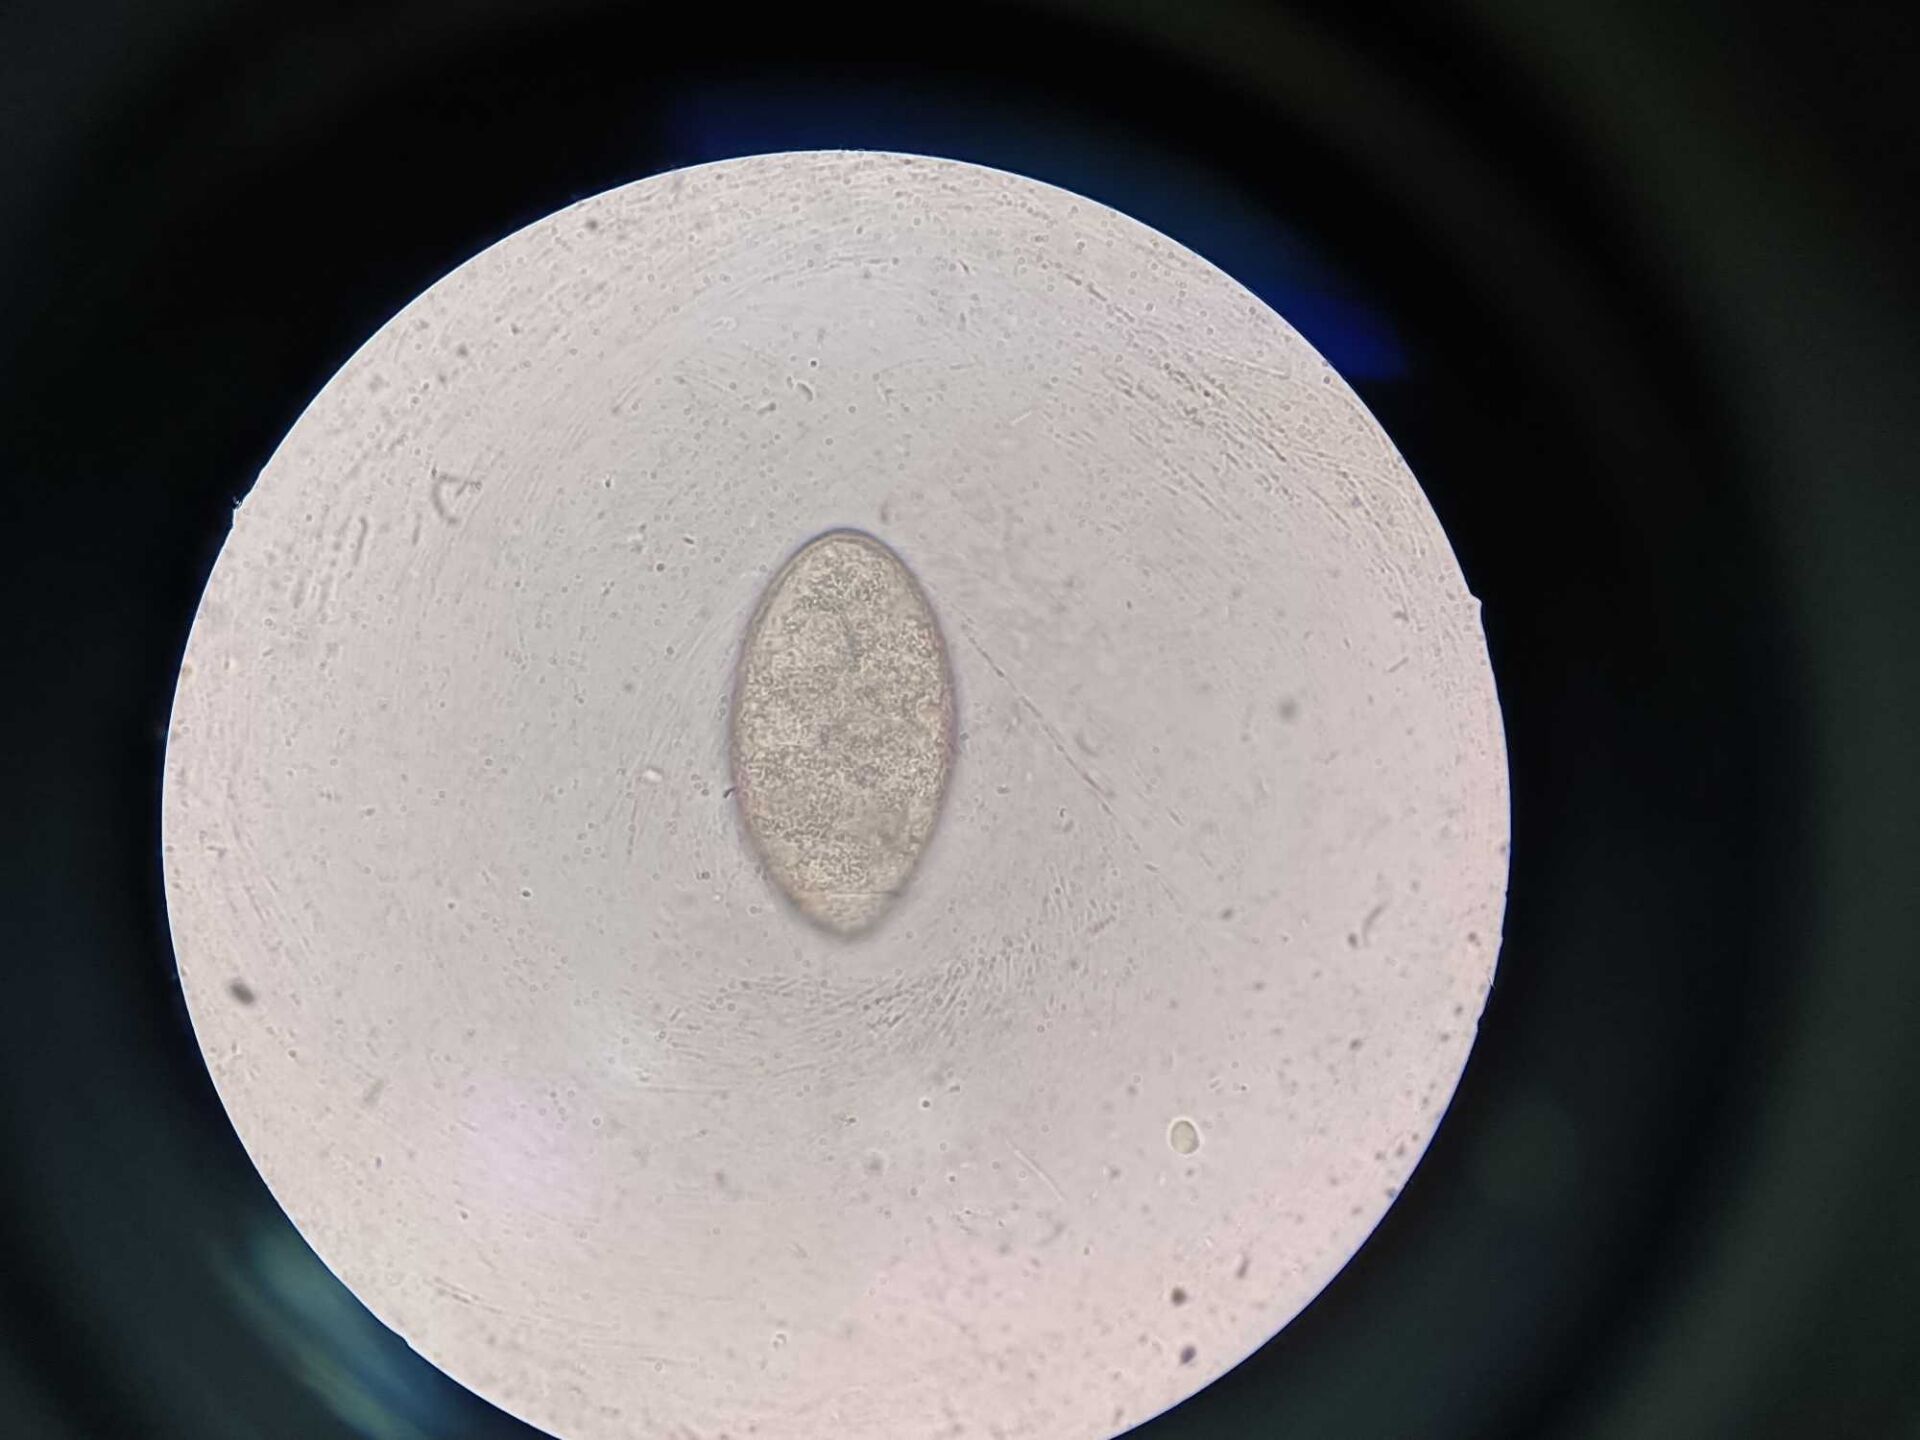

粪便检查病例图片

1.蛔虫卵

2.球虫卵

3.绦虫卵

4.蛲虫卵

5.贾第鞭毛虫

6.钩虫